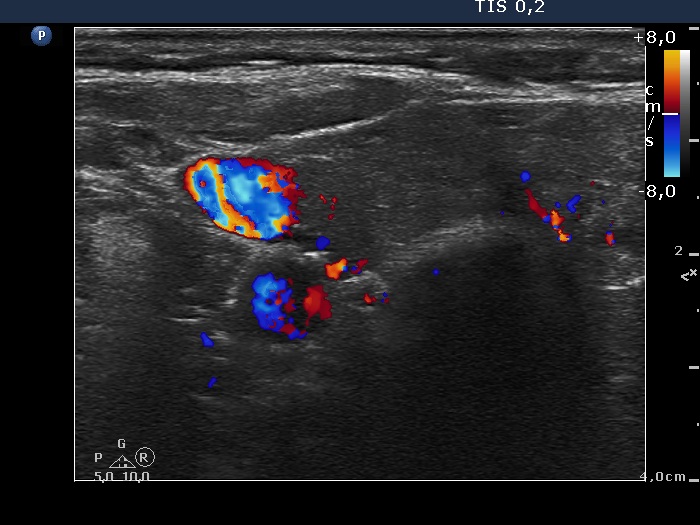

Right lobe, longitudinal scan

Right lobe, transverse scan, color Doppler mode. The vascularization is decreased.